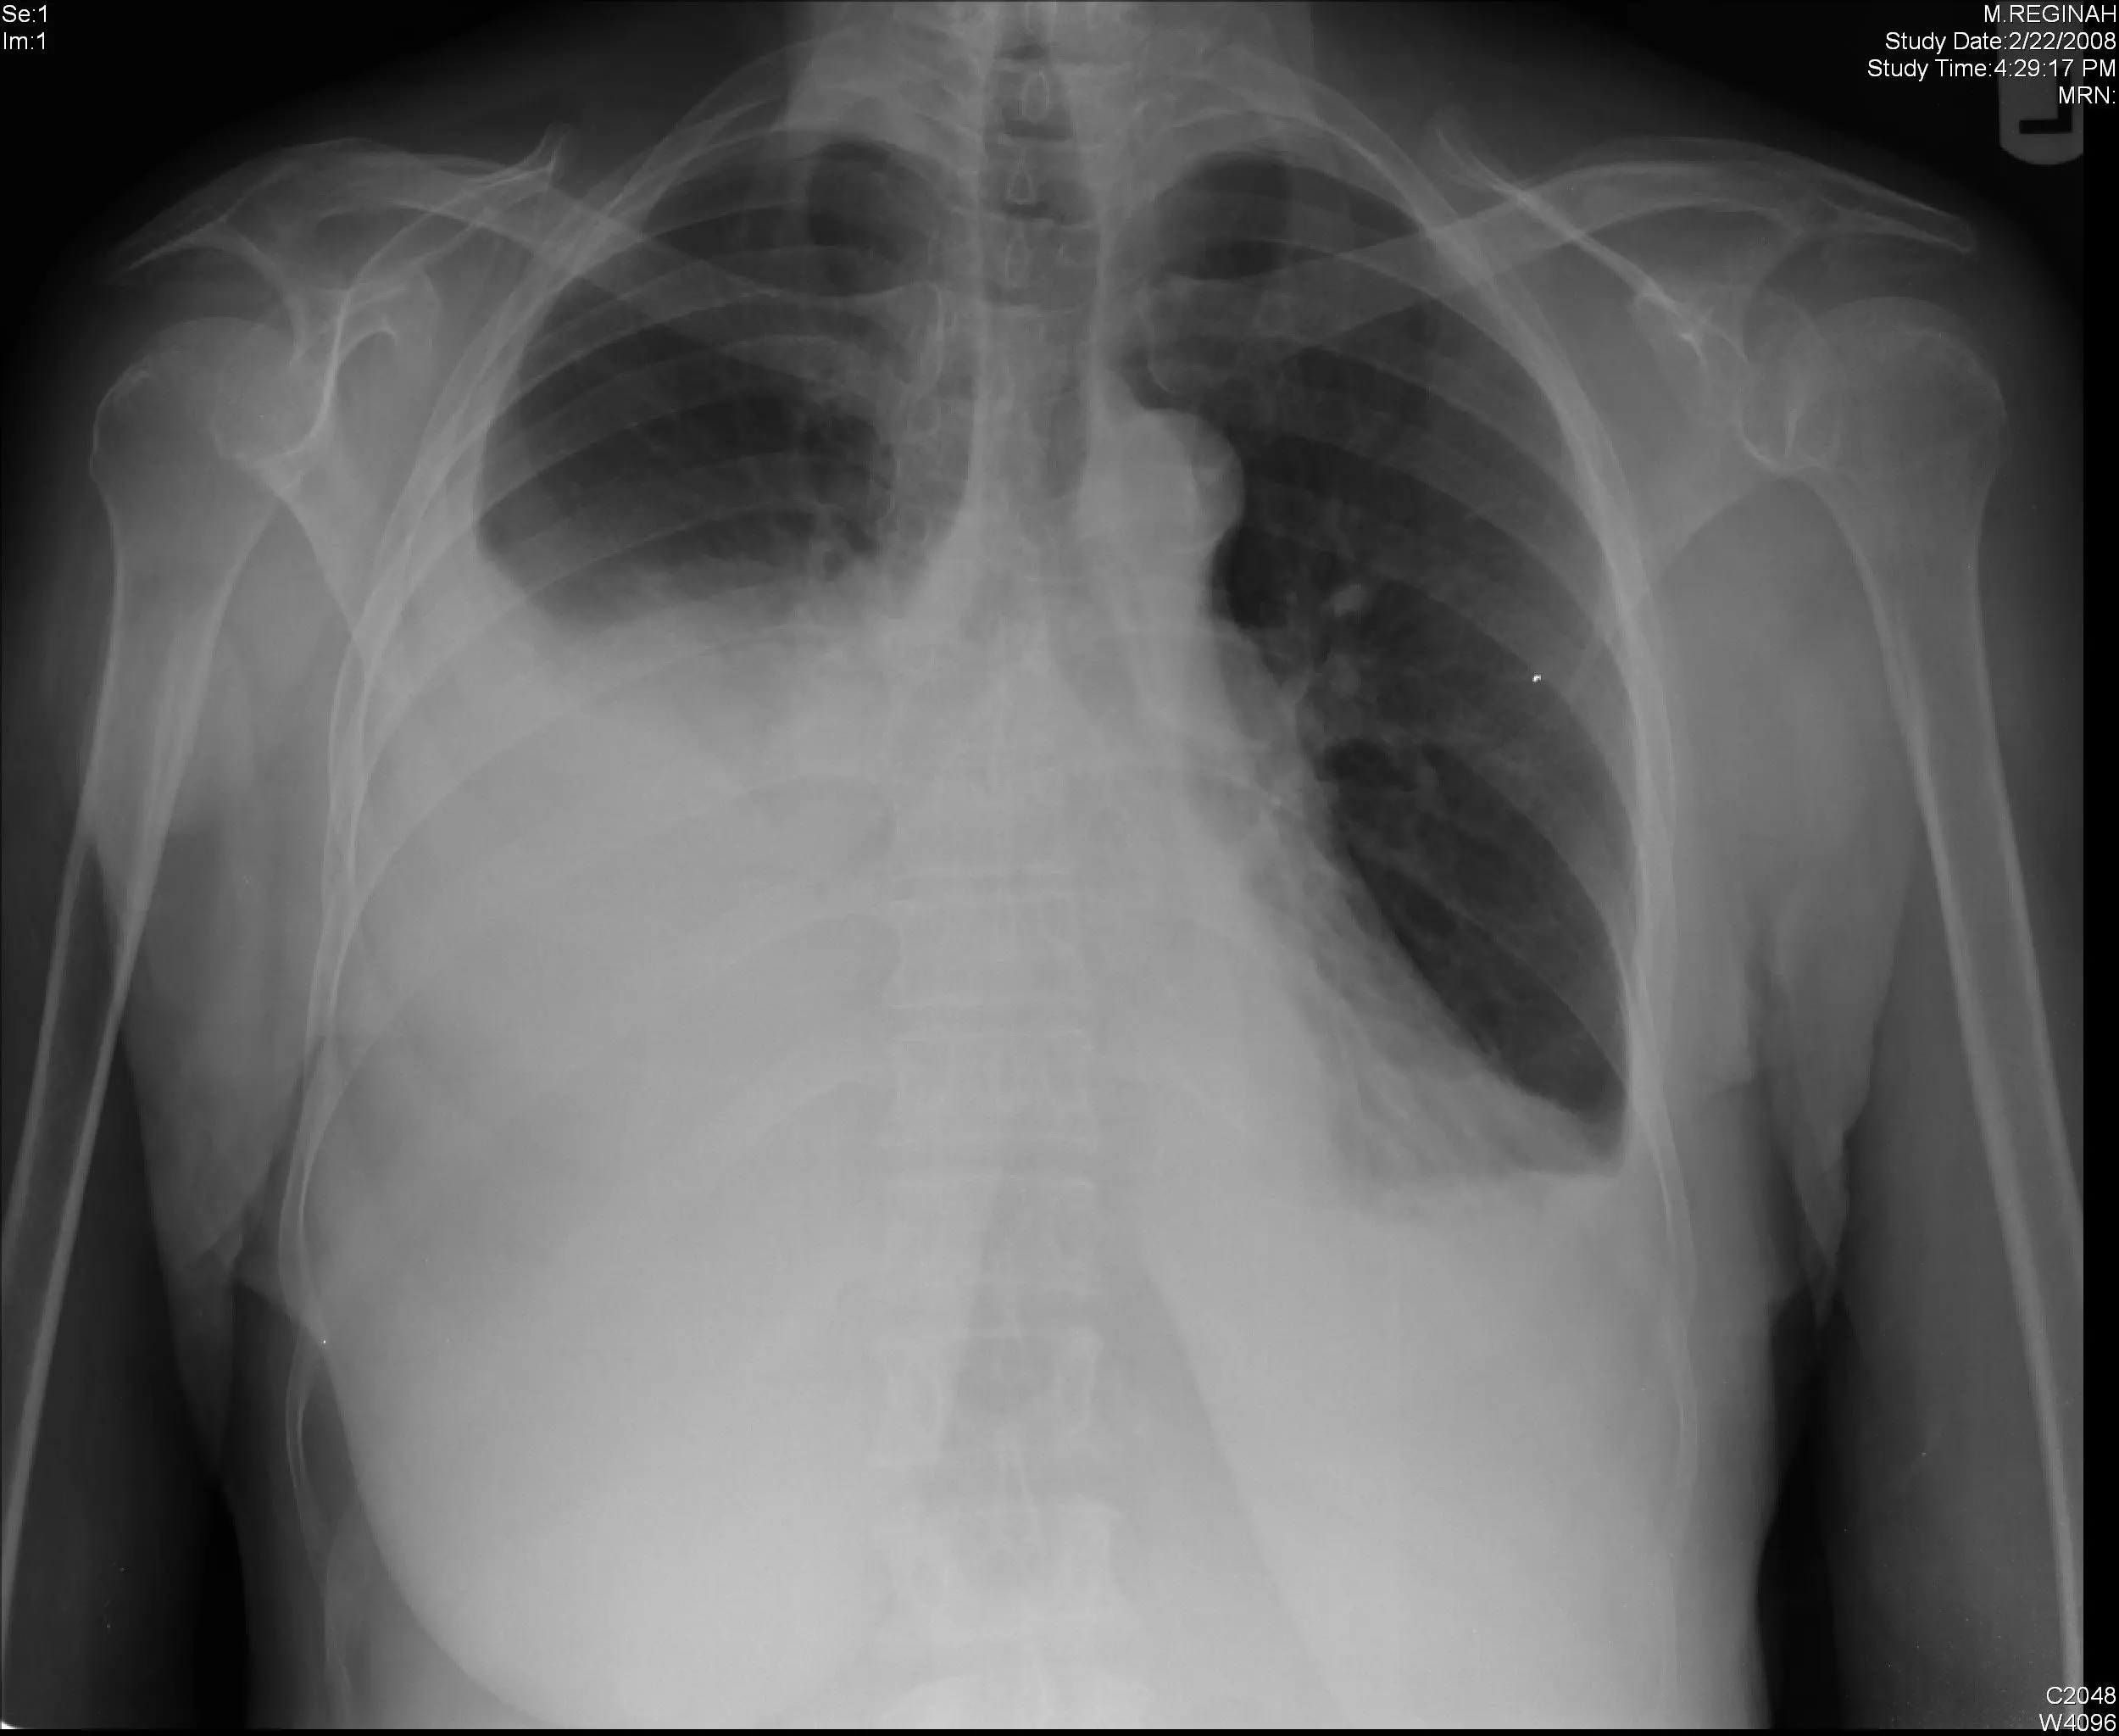

Image - A chest radiograph showing a right-sided pleural effusion. The cardiophrenic and costophrenic angles are completely lost, and a menisci can be seen at the superior margin of the effusion

Creative commons source by Yale Rosen [CC BY-SA 4.0 (https://creativecommons.org/licenses/by-sa/4.0)]